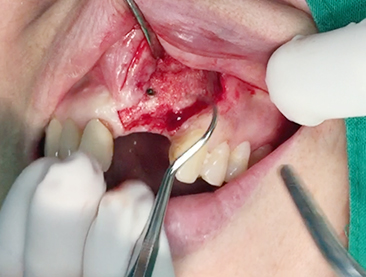

Simultaenous bone grafting for implants

Implants/Bone Grafting

Partial edentulous clinical cases